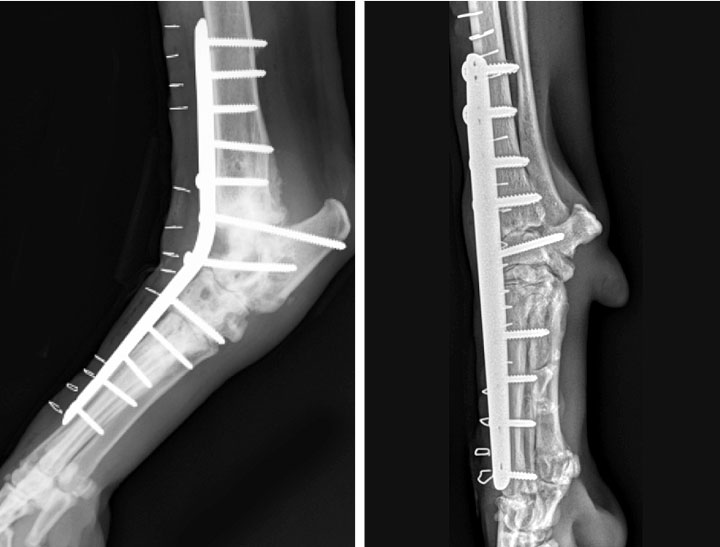

FIGURE E Postoperative partial carpal arthrodesis anterior to Dog Carpal Arthrodesis The fusion of low motion joints in the carpal joints of your dog is referred to as pancarpal arthrodesis. The top image shows a normal limb undergoing stress radiography. These issues can lead to the deterioration of the joint beyond repair. Pancarpal arthrodesis is the established procedure for treatment of carpal hyperextension injuries in small animals; The most common condition. Dog Carpal Arthrodesis.

Dorsopalmar view of the left carpus in a dog demonstrates pancarpal Dog Carpal Arthrodesis In the affected contralateral limb, the resultant angle of extension is greater. The most common condition necessitating carpal or tarsal arthrodesis is a hyperextension injury, in which the ligaments. Dogs with carpal hyperextension have a noticeable bend at the wrist, forcing their lower limb into an abnormally flattened position. The carpal, or wrist, joint in a dog is susceptible both. Dog Carpal Arthrodesis.